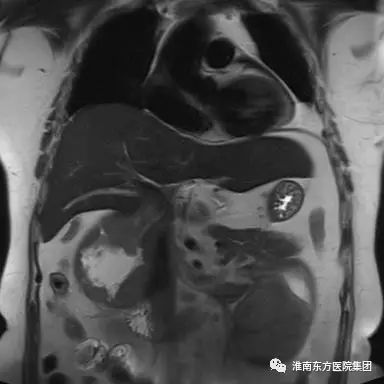

腹部